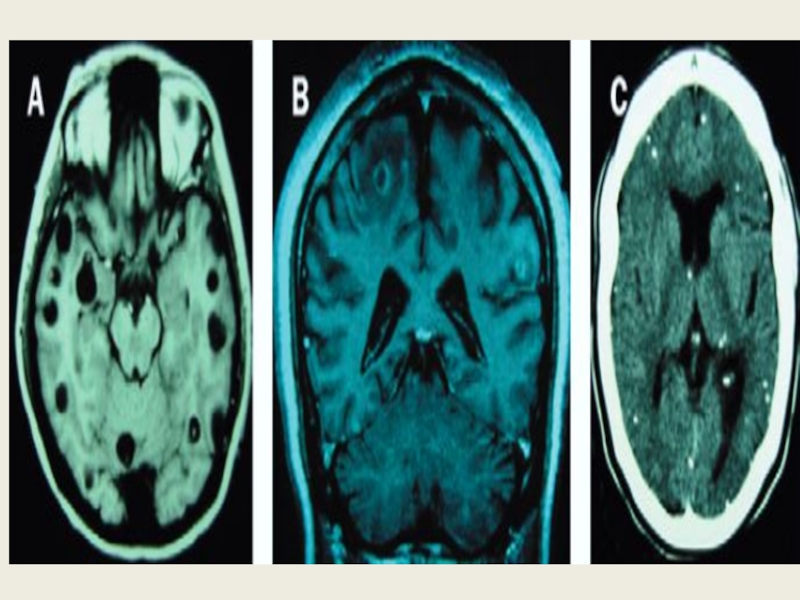

Механічний вплив (ехінококова киста в печінці зростає, здавлює сусідні органи; цистицерки в головному мозку)

—механічним пошкодженням тканин у зоні паразитування гельмінтів. Це супроводжується

запаленням, атрофією тканин, порушенням функцій різних органів і систем. Так, локалізація цистицерка в речовині мозку, в оці призводить до порушення функції цих органів, закупорка просвіту кишечника аскаридами — до розвитку кишкової непрохідності, в місці проживання волосоголовця розвивається запальна реакція, проявом якої може бути апендицит, тощо;